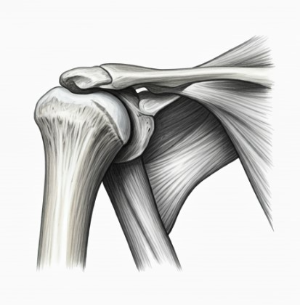

연골은 관절을 부드럽게 움직일 수 있도록 도와주는 쿠션 역할을 합니다. 그러나 나이가 들수록 연골은 자연스럽게 닳거나 손상되면서 관절의 마찰과 통증을 유발하게 됩니다. - 근육량 감소

특히 갱년기에 접어드는 여성은 호르몬 변화로 인해 골밀도가 낮아지고 관절의 유연성과 탄력성이 감소하게 됩니다. 이러한 변화는 관절 질환의 위험을 높입니다.